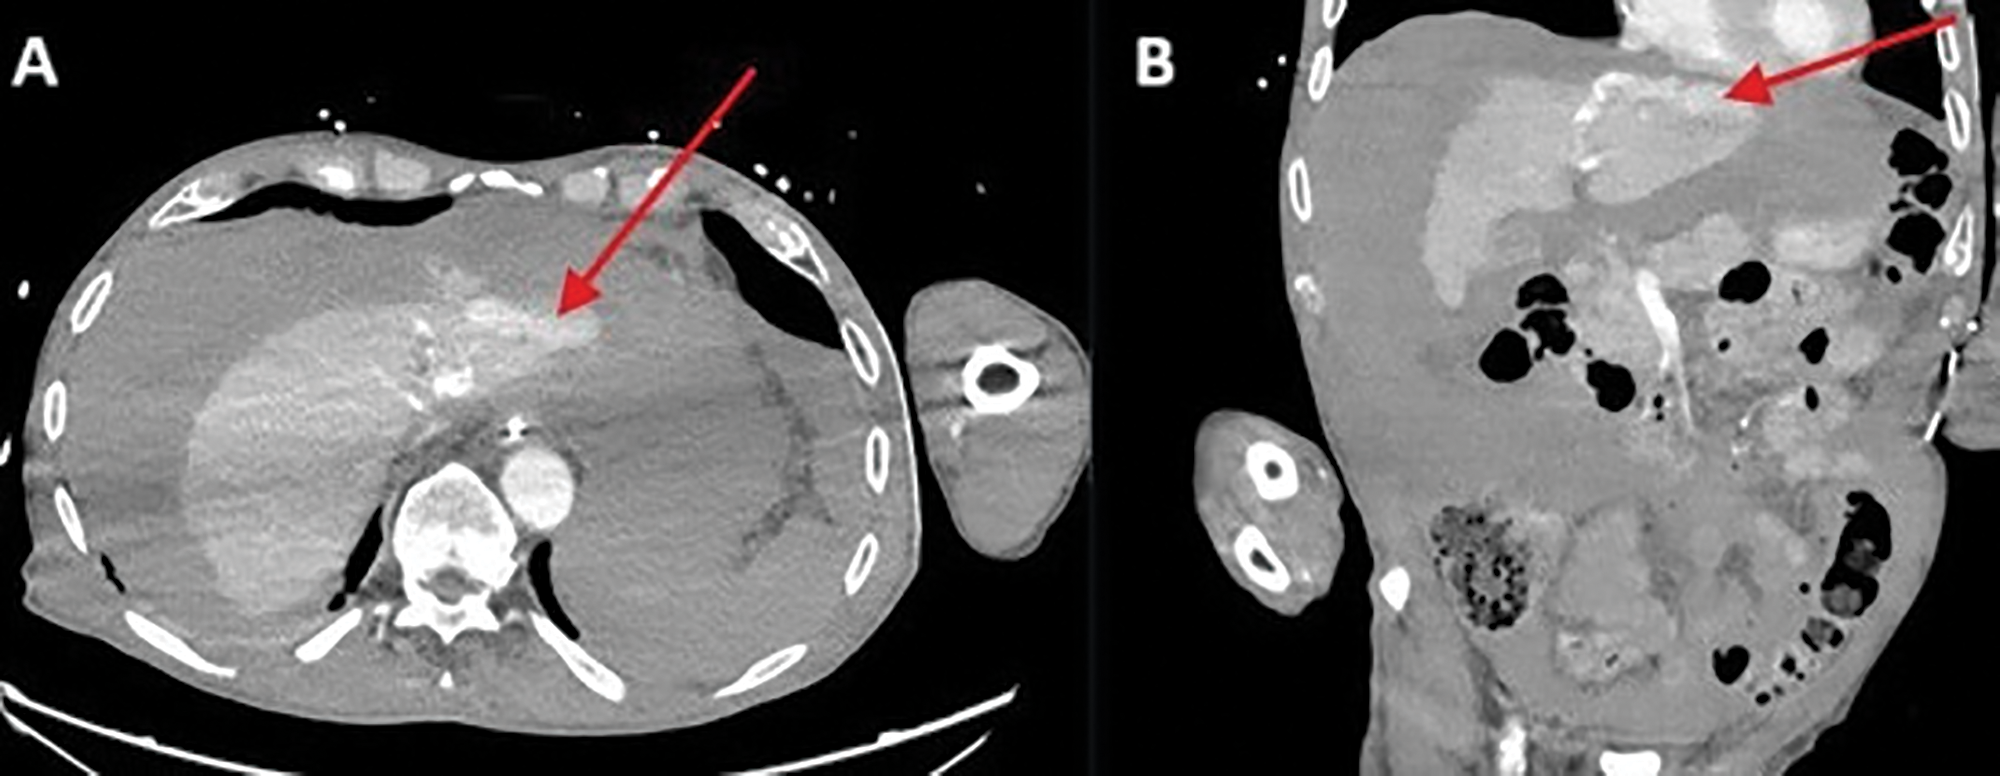

A 78‑year‑old man was referred to the emergency department for cardiac arrest. Return of spontaneous circulation (ROSC) was achieved following manual cardiopulmonary resuscitation (CPR). Coronary angiography revealed three‑vessel disease; the procedure was largely challenging due to a difficult femoral artery access by pronounced calcified atheromatosis. In the following hours, the patient developed progressive hemodynamic instability, accompanied by a decline in haemoglobin. An abdominal bed‑side ultrasound revealed diffuse hyperechogenic fluid in the perihepatic, perisplenic, and lateral areas, as well as in the Douglas pouch, indicating diffuse hemoperitoneum. Computer tomography angiography (CTA) of the abdomen revealed active venous contrast extravasation against the left hepatic lobe (Figure 1 A, B; red arrow).

Figure 1

Active venous contrast extravasation against the left hepatic lobe.